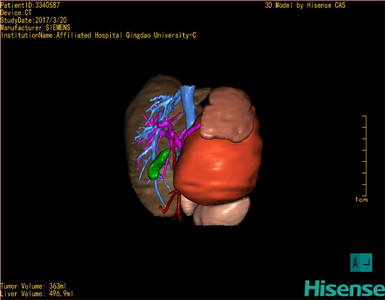

将0.625mm双源薄层CT资料的静脉期和动脉期Dicom格式文件导入海信CAS系统。

通过调节窗宽窗位调整CT序号,对肿瘤,肝实质,胆囊,下腔静脉,肿瘤,肝动脉、门静脉及肝静脉等进行三维重建;系统自动计算肿瘤体积和肝脏体积。

模拟手术操作,自动计算切除肿瘤体积。肝脏体积为496.9ml,肾上腺肿瘤体积363ml,术前规划手术方案,进行手术。

术前三维重建:

重建图片